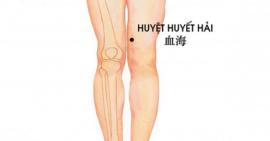

Trị đau khớp gối tại nhà bằng phương pháp bấm huyệt bạn đã biết chưa?

Có rất nhiều phương pháp trị đau khớp gối được lưu truyền đến ngày nay. Trong đó có phương pháp bấm huyệt cũng được nhiều người...